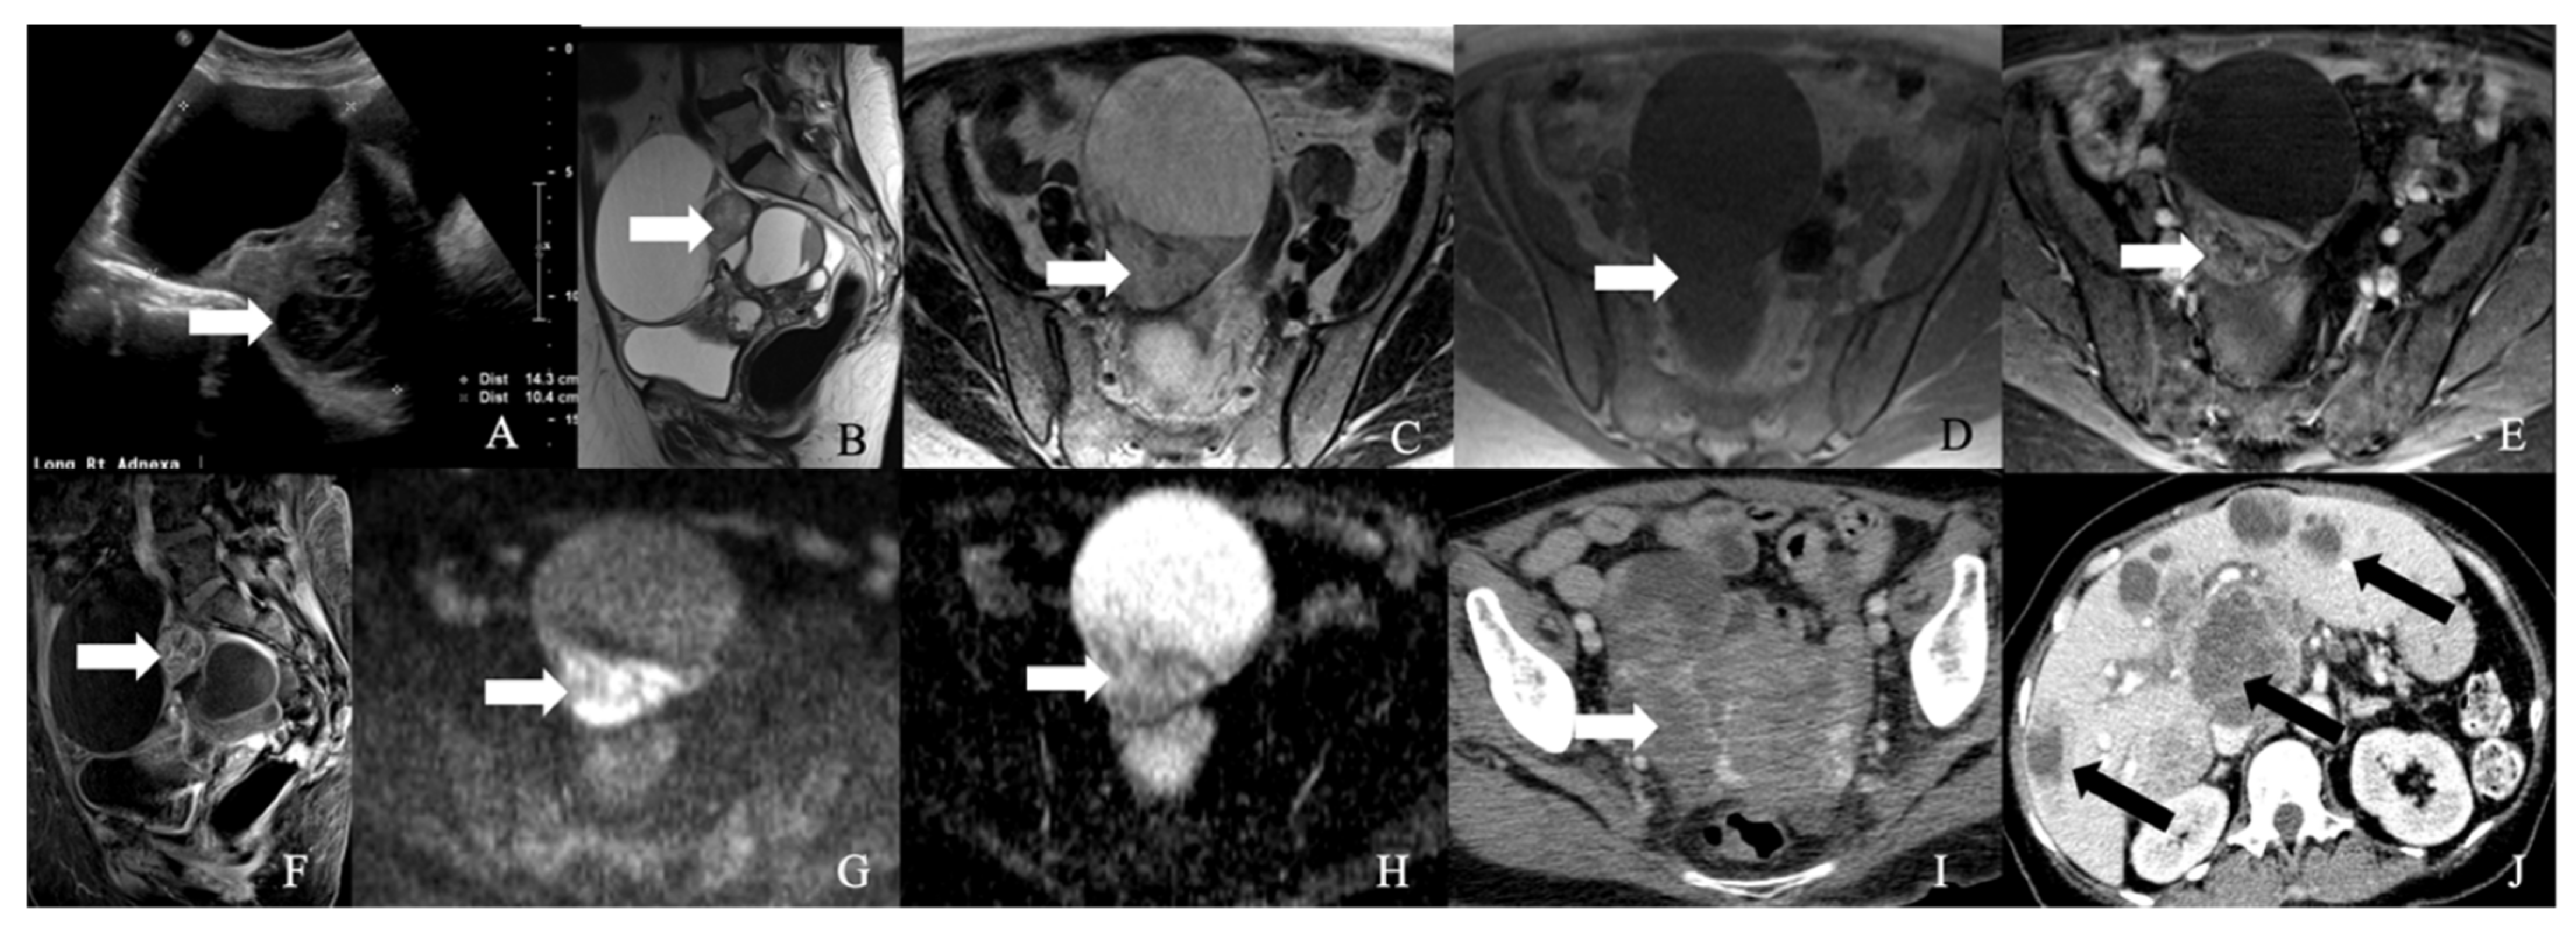

5.1. Ovarian Carcinoid Tumors

Most ovarian NENs are benign carcinoid tumors that arise from dermoid cysts [11] (Figure 7). Ovarian carcinoids can be a primary or metastatic tumor. Primary ovarian carcinoids (POC) are more common than metastatic tumors, constituting 0.1% of the ovarian neoplasms [89]. Most POC manifest as a small, lobulated, solid, and unilateral soft tissue lesion in a dermoid cyst. Upon gross inspection, a larger POC may be visible as a yellow nodule [11]. Metastatic ovarian carcinoids can be frequently observed in patients with a history of carcinoid tumors in the midgut. They often present as bilateral, nodular masses with extensive lymphovascular and extra-ovarian involvement [11]. The five-year survival rate of ovarian carcinoid is 84% and 94% in patients with and without dermoid, respectively [90]. Morphologically POC comprises insular, trabecular, stromal, and mucinous carcinoid variants. The pathological features of these variants are described in Table 7 [11].

5.3. Management

Due to the rarity of ovarian NENs, the literature consists of case reports and small case series. The majority of small-cell NEC presented in peri- or post-menopausal women underwent hysterectomy with bilateral salpingo-oophorectomy and debulking as a part of the management [8]. Table 9 and Figure 8 describe FIGO staging, and Figure 9 and Figure 10 illustrate the diagnostic and treatment algorithms for ovarian NENs. In a study by Pang et al., the five-year overall survival and cancer-specific survival after surgery were 97% and 97%, respectively, in patients with early-stage ovarian NENs [94]. In cases of advanced disease, comprehensive treatment comprising surgery, chemotherapy, and radiotherapy was associated with an improved five-year overall (73%) and cancer-specific (70%) survival [94]. In a study including 11 case reports, age, AJCC stage, mode of treatment, and histological type were the significant prognostic factors for ovarian NENs [94].